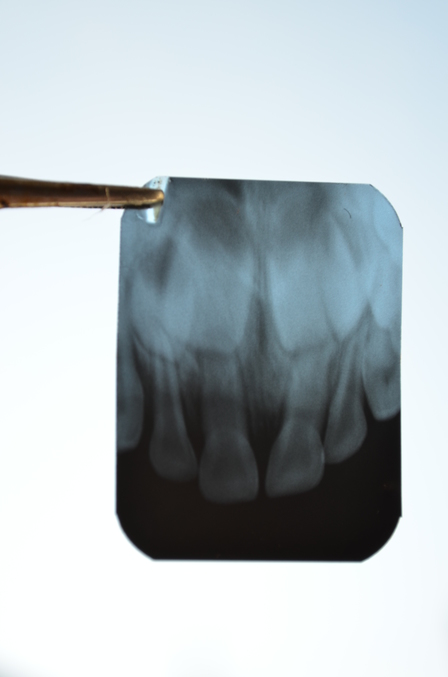

Здравствуйте! Моя дочечка упала, ударилась верхней челюстью, шла кровь из 2 передних верхних зубиков, опухла и посинела внутри губа, повреждена уздечка. Суббота, вечер. Дождались утра, поехали в государственную стоматологию. Осмотрела врач, зубы не шатались, помазала хлорофиллиптом и посоветовала полоскать ромашкой. Через пару недель отёки и синяки прошли, но 2 передних зуба изменили цвет, они немного посинели, как бы изнутри. Ребёнок до сих пор не кусает ими твёрдую пищу. Обратились в частную клинику, хотя они и предупредили, что детей не лечат. Нам сделали рентген. Сказали, что перебиты нервы, от этого зубы отмерли и потемнели, что они ещё больше потемнеют, что они упёрлись в зачатки постоянных зубов или удар спровоцировал рост постоянных зубов. Рвать зубы показаний нет, мол нет нагноения и прочего. Но идёт процесс расшатывания зубов... Переживаниям моим нет предела. Что делать? Как быть? Судя по снимку, хоть я не врач, второй зуб, левый, как бы вошёл внутрь десны (его немного перекосило с наружи). Можно ли хоть каким то образом затормозить потемнение зубов? Нарушены ли зачатки постоянных зубов? Мне кажется, что они разошлись и вырастут криво. Принимать ли кальций?